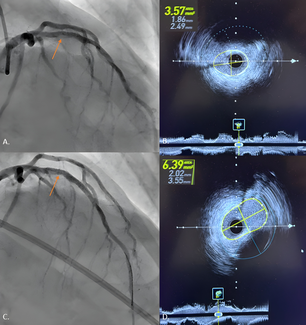

The authors present a case series with off-label use of Shockwave Intravascular Lithotripsy (Shockwave Medical) in acutely under-expanded stents.